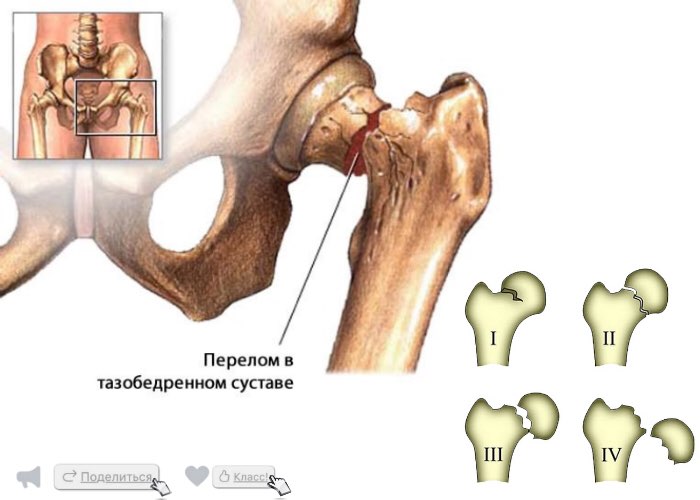

Классификация переломов диафиза бедренной кости: Иллюстрации и информация